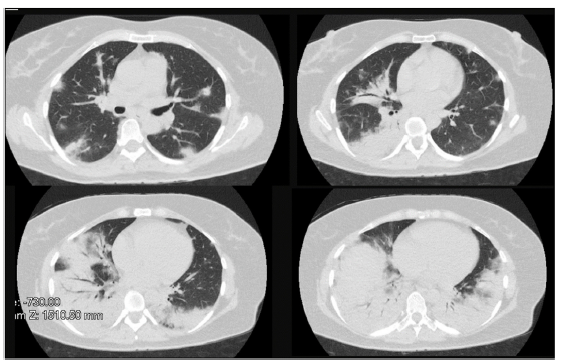

A 50-year-old female patient, consultation due to a medical condition of 2 months of evolution consisting of intermittent episodes of dry cough, associated with dyspnea and deterioration of its functional class, MMRC 4, she does not report fever, subjective weight loss, for which she is directed from external consultation to the emergency service. Within her antecedents she does not mention chronic pathologies, no smoking or biomass exposure, highlights hysterectomy plus pomeroy for uterine myomatosis. She enters the emergency service in regular general conditions, broken speech, blood pressure (Pa): 115/70 mmHg, heart rate (h) 80 beats per minute (bpm), breathing frequency (fr) 22 breaths per minute (rpm), oxygen saturation 89-90% with ambient oxygen, the lung auscultation reveals the presence of velcro crepitus in both lung bases, paraclinical tests that show normal leukocytes, no anemia, PCR 1.67, preserved kidney function. A high-resolution chest tomography was performed (TACAR) (Fig. 1) where consolidative images were described predominantly in the lung bases, presence of air bronchogram, associated with subpleural nodules, it is initially considered a manifestation of community-acquired pneumonia, the presence of risk for Gram positive germs is also considered under the suspicion of septic seeding. Despite the antibiotic treatment, no improvement was observed in his clinical condition. It is considered that in the onset of his condition there is no presence of symptoms suggestive of an ongoing infectious process, and because it is a chronic dyspnea associated with tomographic findings, the possibility of organizing pneumonia is raised, she was taken to bronchoscopy plus biopsy, as well as percutaneous biopsy. In order to clarify the etiology of her condition, she was questioned about drug use, radiation exposure, malignancy and paraclinical tests with an autoimmunity profile were complemented (Table 1), which is normal. A percutaneous lung biopsy report was obtained with a histological pattern consistent with organizing pneumonia (Fig. 3). Management is started with methylprednisolone in boluses of 500 mg iv day for 3 days, then she switched to oral corticosteroid, with which an improvement in her dyspnea and radiological improvement was observed (Fig. 2), she is discharged with corticosteroid and home oxygen management. During outpatient follow-up, pulmonary function test is performed: CVF: 60%, DLCO: 15%. The patient abandoned the treatment by her own decision, presenting worsening of her dyspnea and appearance of joint pain and Raynaud's phenomenon. Autoimmunity profile is performed again, this time the report is positive for Anti Jo and Anti RO, the patient is considered to meet Solomon criteria for which antisynthetase syndrome is diagnosed. Faced with a new episode of relapse, she is hospitalized and a cycle of intravenous cyclophosphamide is started, with which she has presented improvement in her disease pattern.

Characteristic radiographic findings within organizational pneumonia consist of ground glass opacities (88%), consolidation (83%), peribronchovascular opacities (52%), reticular infiltrates (38%) bronchiectasis (33%), interstitial nodules (27%), reverse halo sign (17%). Being the compromise predominantly in the lower lobes and subpleural distribution.7,8 One of the important characteristics regarding radiological evolution is that the findings have a changing pattern over time. As can be seen in Figs. 1 and 2, a pattern of pulmonary consolidation is presented with greater involvement of the pulmonary bases, with presence of subpleural nodules and small areas of ground glass.

Fig. 1 First tomography. Consolidative images were described predominantly in the lung bases, presence of air bronchogram, associated with subpleural nodules.